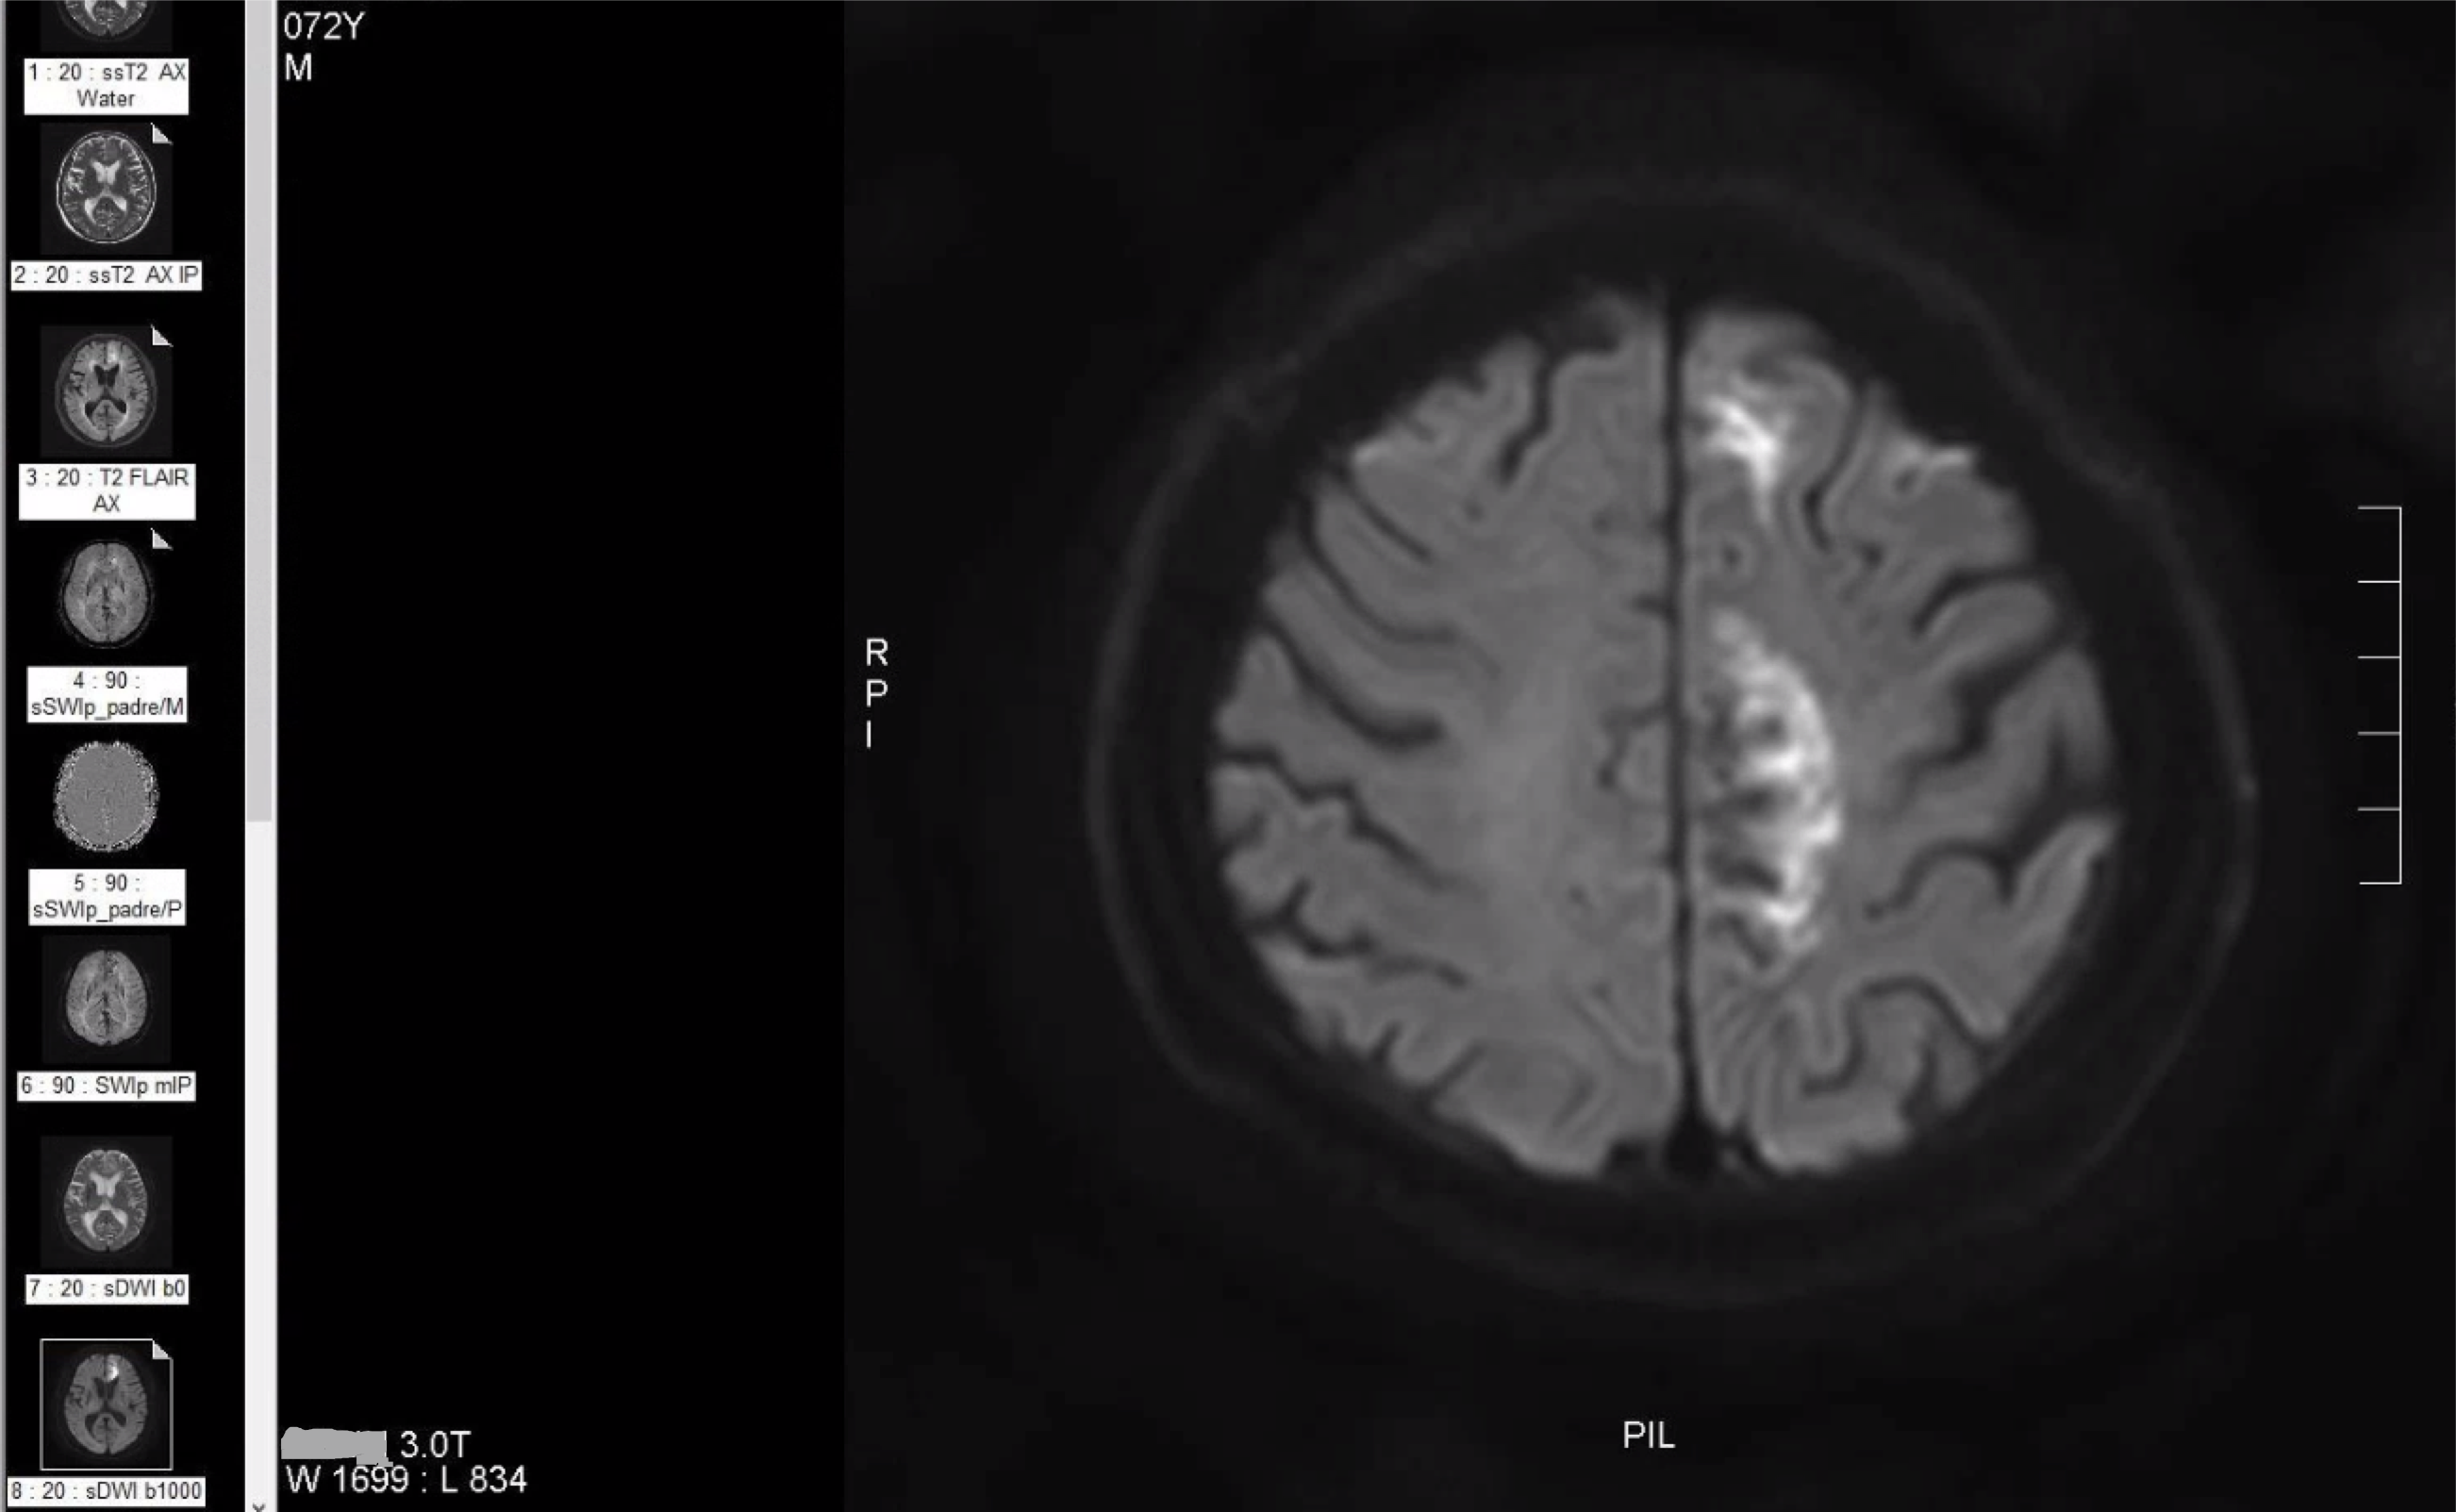

M/72

right hemiplegia d/t cbr infarction 2019.9.3.

left ACA territorry infarction